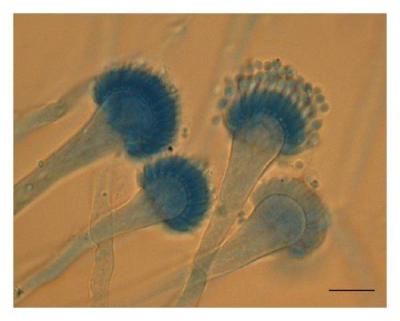

दिल्लीत नव्या फंगसमुळे होणाऱ्या मृत्यूंमुळे चिंतेत भर पडली आहे. एम्समध्ये दोन रुग्णांना एस्परजिलियस लेंटुलस नावाच्या फंगसची लागण झाली. या प्रकारच्या फंगसवर कोणत्याही औषधाचा परिणाम होत नाही.

क्रॉनिक ऑब्स्ट्रक्टिव पल्मोनरी डिजीजचा सामना करत असलेल्या दोन्ही रुग्णांचा उपचारादरम्यान मृत्यू झाला. एस्परजिलियस लेंटुलस फुफ्फुसावर परिणाम करतं. २००५ मध्ये वैद्यकीय जगताला या फंगसची औषध पटली. तेव्हापासून आतापर्यंत अनेक देशांमध्ये एस्परजिलियस लेंटुलसचे रुग्ण आढळून आले आहेत.

भारतात पहिल्यांदाच एस्परजिलियस लेंटुलसचे रुग्ण आढळून आले आहेत. इंडियन जर्नल ऑफ मेडिकल मायक्रोबायोलॉजीमध्ये (IJMM)प्रकाशित झालेल्या अहवालानुसार एस्परजिलियस लेंटुलसमुळे मृत्यूमुखी पडलेल्या एका रुग्णाचं वय ५० ते ६० वर्षांदरम्यान, तर दुसऱ्या रुग्णाचं वय ४५ वर्षांपेक्षा कमी होतं.

बुरशीमुळे होणाऱ्या आजारांना फंगल इन्फेक्शन म्हटलं जातं. बुरशी पर्यावरणात आढळून येते. बुरशीमुळे होणारे बरेचसे संसर्ग लगेच बरे होतात. मात्र काही संसर्ग अतिशय घातक ठरतात. त्यामध्ये कँडिडा किंवा एस्परजिलियस फंगसमुळे होणाऱ्या संसर्गाचा समावेश होतो.